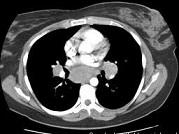

问题 女,33岁,咳嗽,乏力,低热,皮肤有结节,结合CT图像,最可能的诊断是 ( )

选项 A.肺结核 B.霍奇金病 C.非霍奇金病 D.结节病 E.肺癌

答案 D